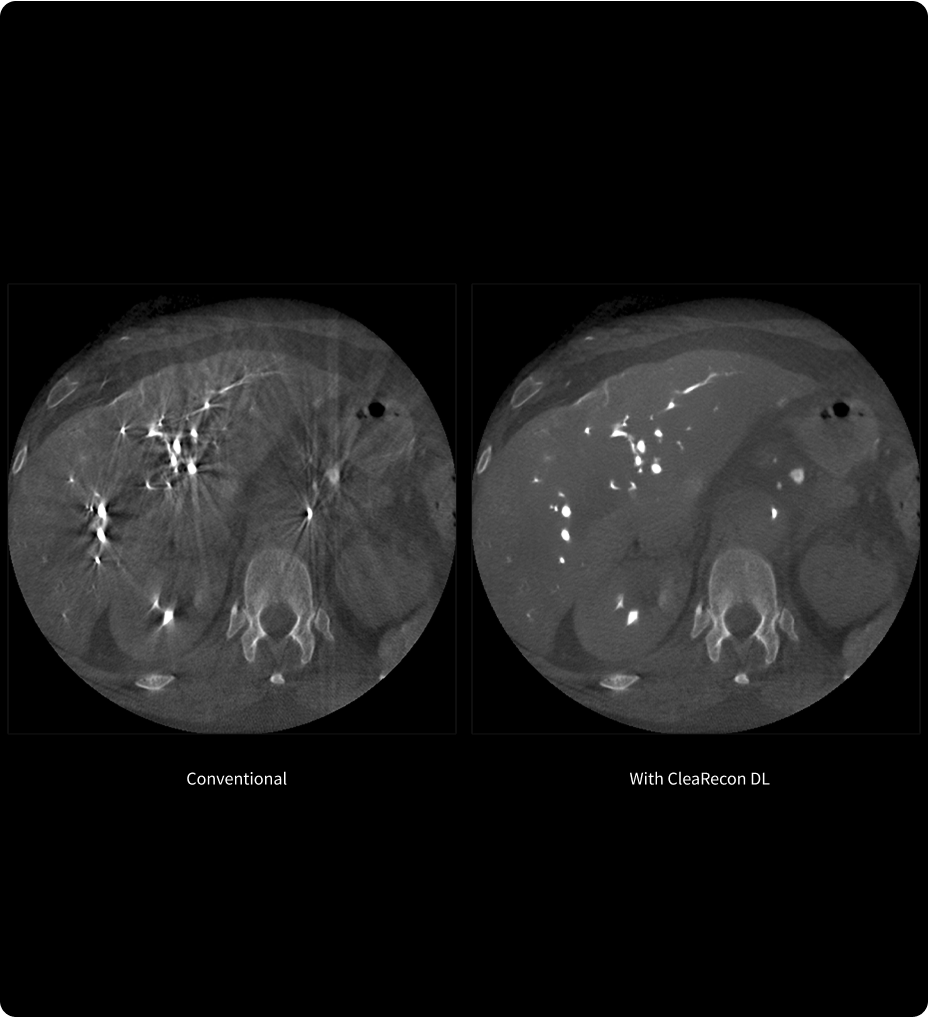

Qualité d'image

Très efficace en imagerie à l’état stable comme en imagerie dynamique 2-6,12

La haute relaxivité de Pixxoscan constitue un avantage pour l’amélioration des images à l'état stable3-6,12.

Par ailleurs, le bolus plus étroit du gadobutrol est conçu pour optimiser la visualisation lors de l’imagerie dynamique, offrant ainsi des avantages potentiels dans certains contextes cliniques2.